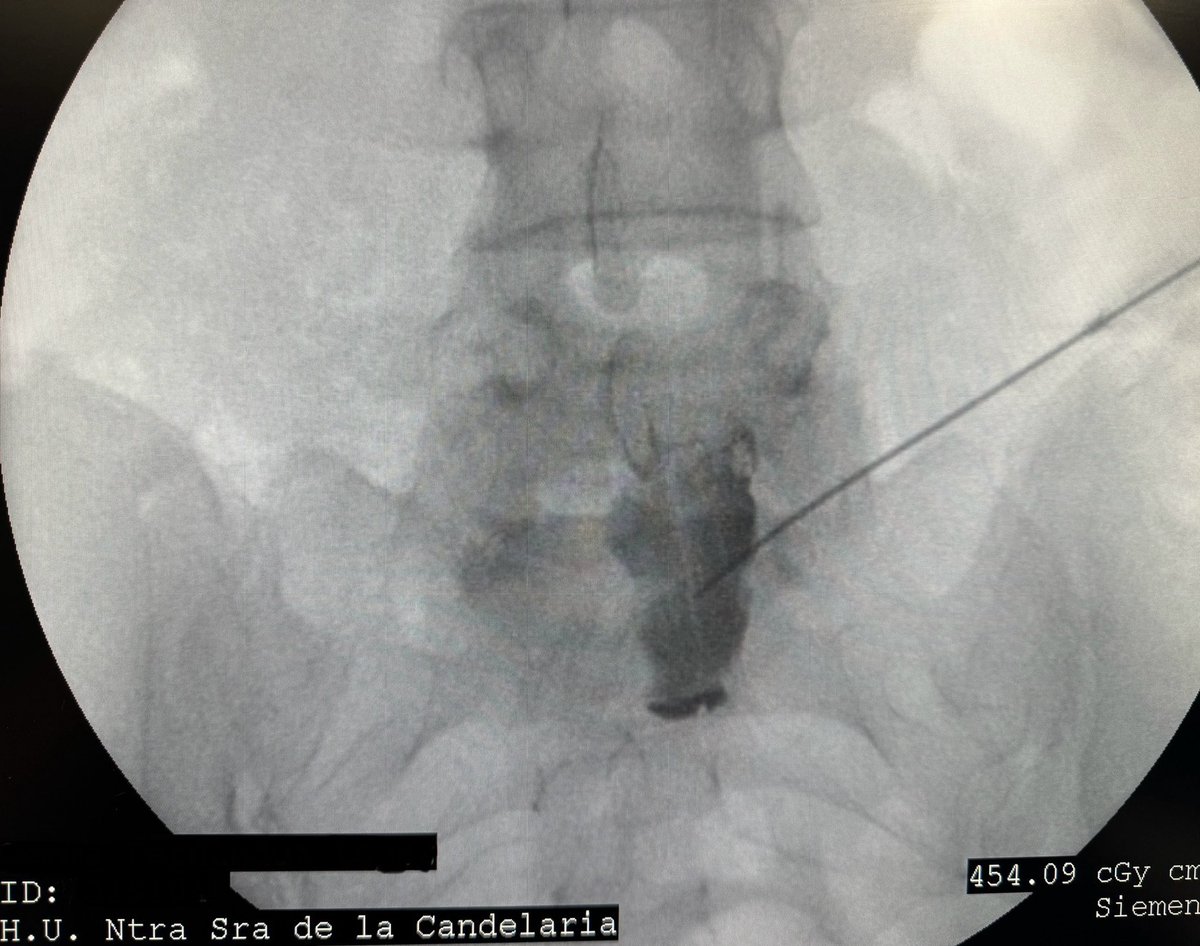

Bloqueo del plexo hipogastrico superior para tratamiento de dolor pélvico crónico. Abordaje transdiscal #dolorcronico #pain

Bloqueo del plexo hipogastrico superior para tratamiento de dolor pélvico crónico.

Abordaje transdiscal

#dolorcronico #pain